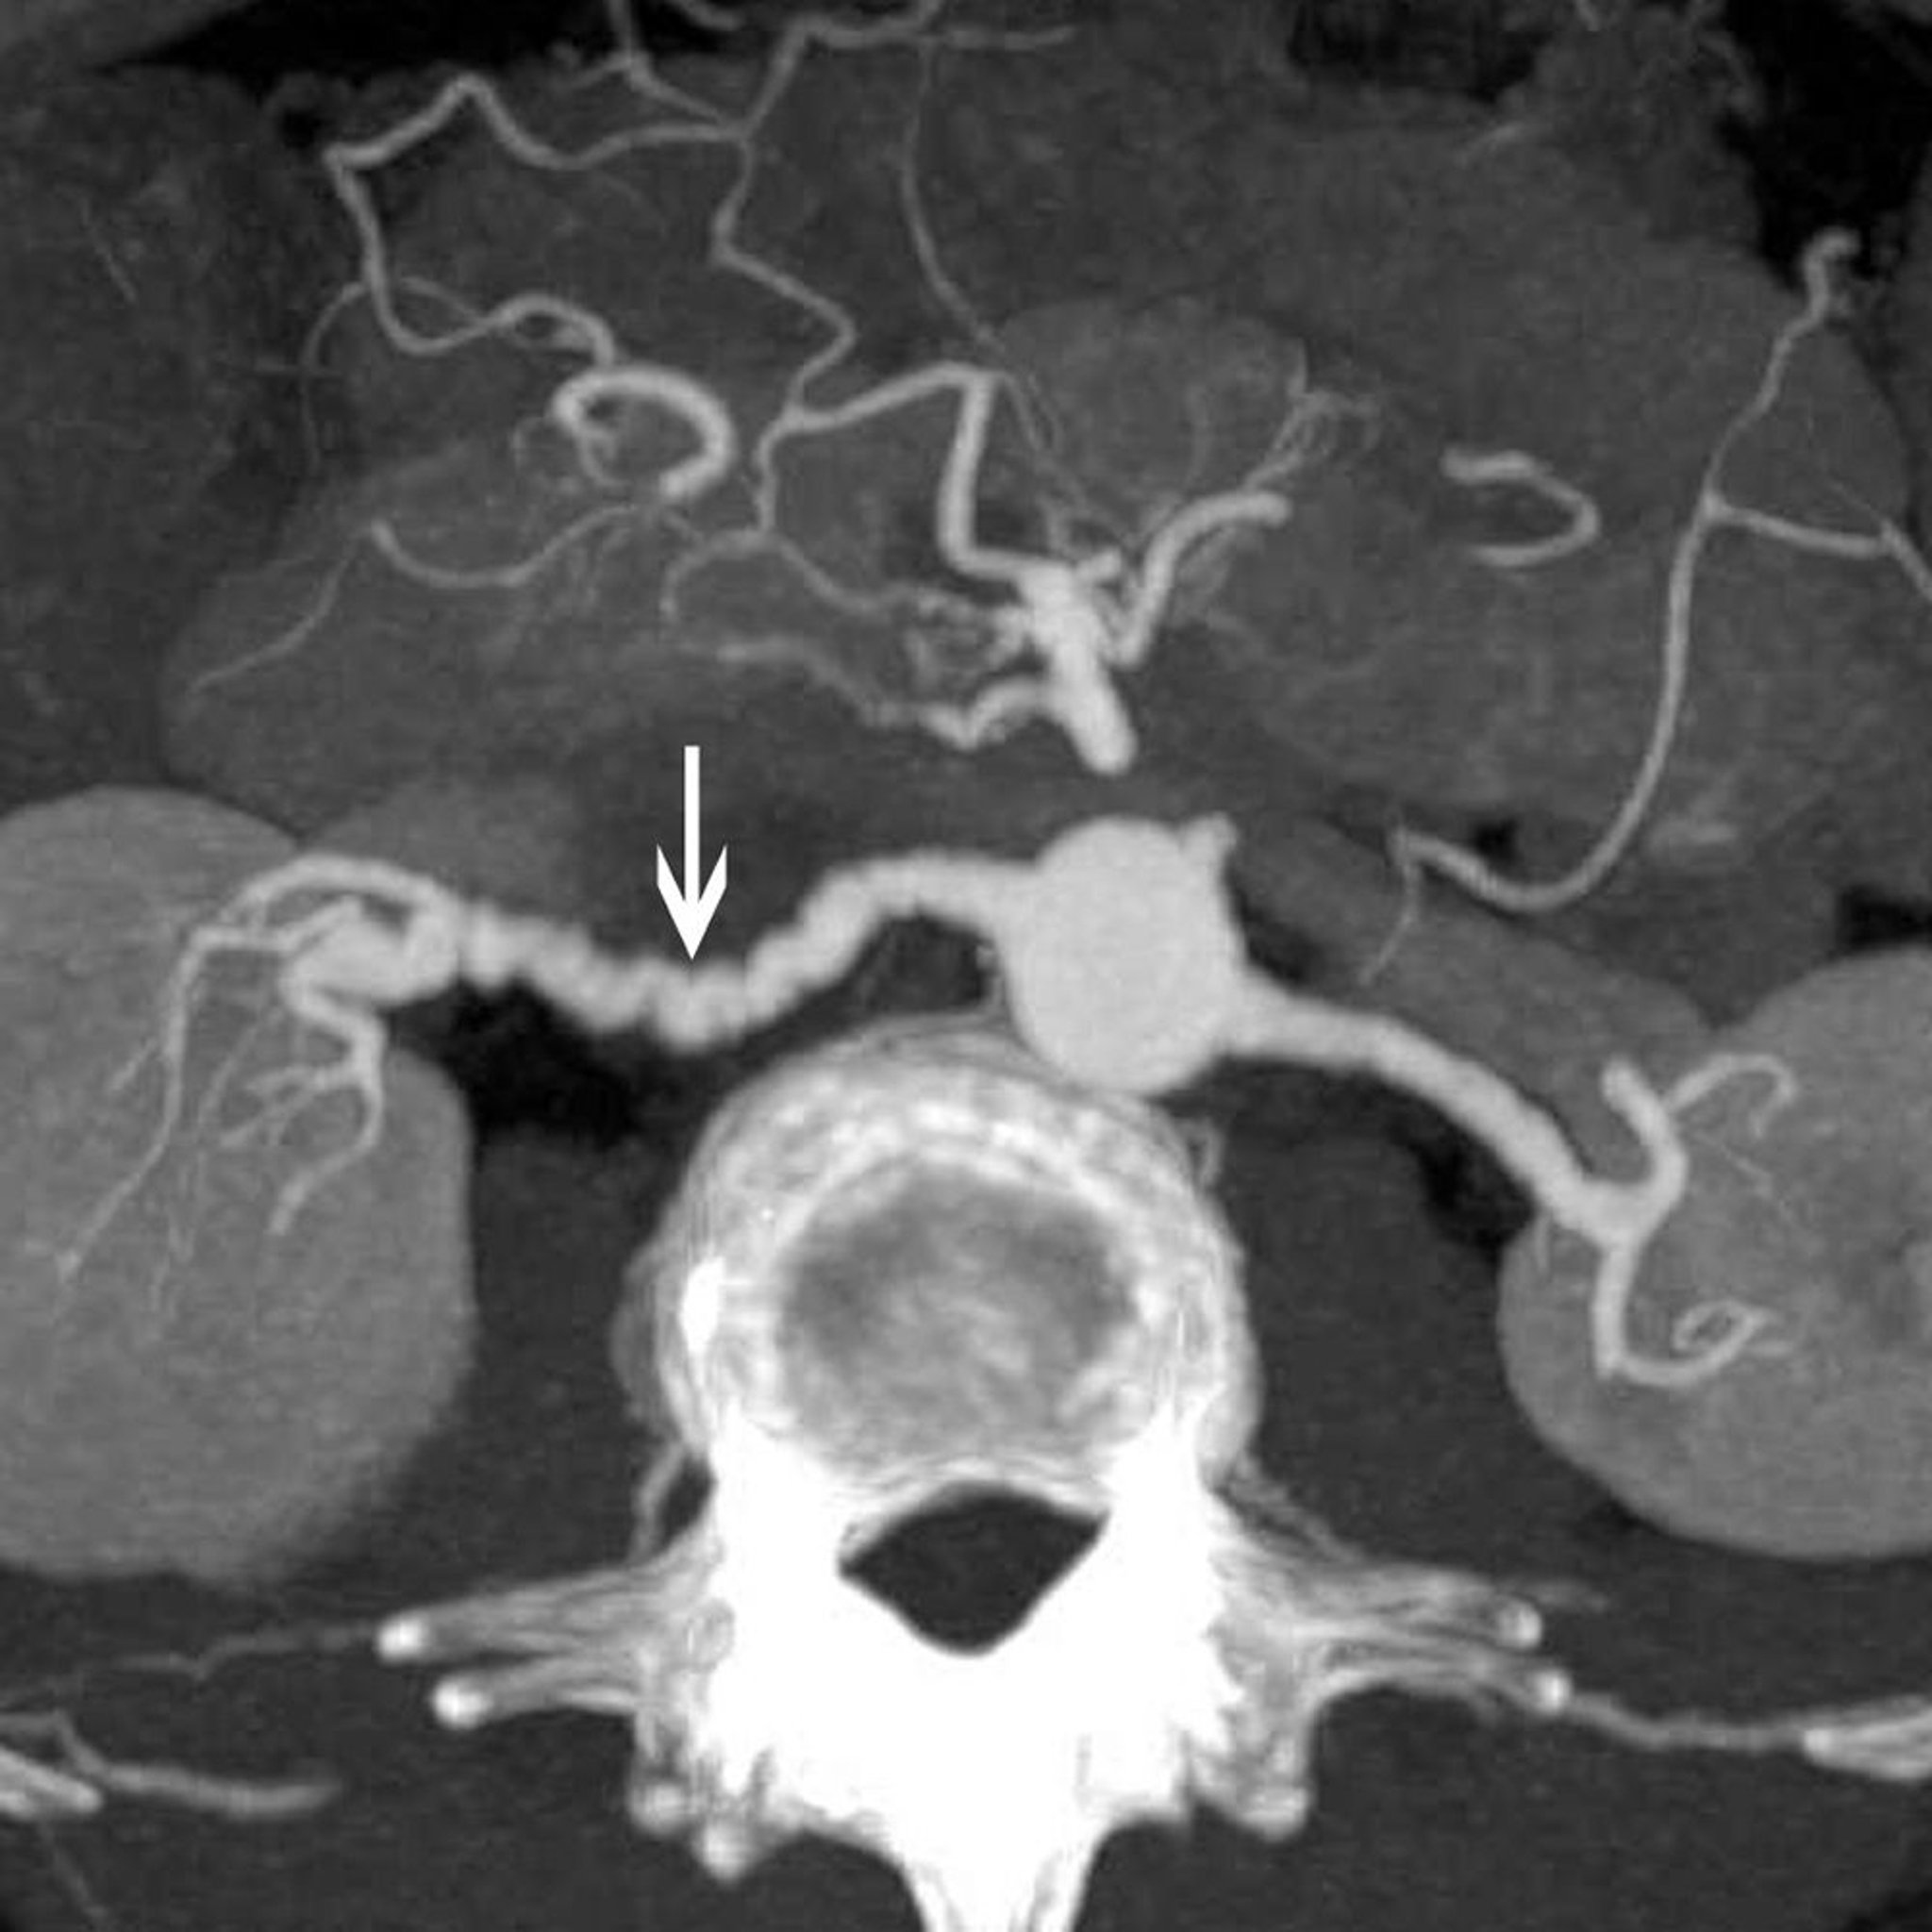

Displasia fibromuscular de la arteria renal

Esta imagen muestra el signo clásico de "collar de cuentas" (flecha) en un paciente con displasia fibromuscular de la arteria renal.